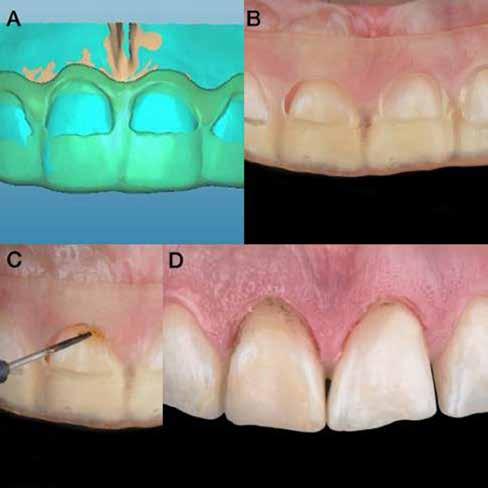

Az előzetes állapotfelmérést és a kezelés megtervezését követően a fogakat minimál invazív módon preparáltuk (1. a-b ábrák), majd az előkészített fogak ínybarázdáiba fonalbehelyező eszköz segítségével (113 Serrated Gingival Cord Packer, Hu-Friedy, Chicago, Illinois) teflonszalagot helyeztünk (Loctite Thread Seal Tape, Henkel Loctite Corp., Egyesült Államok), (1. c ábra). A hagyományos retrakciós fonalak helyett, a rugalmasságuk miatt előnyösebbnek tartjuk a teflonszalagok használatát. A kofferdámot (Dental Dam, Nic Tone, Bukarest, Románia) az előkészített fogakon kívül, az azoktól disztálisan elhelyezkedő egy-egy fognak megfelelően is perforáltuk.

Mivel a felső fogív első kisőrlőfogtól ellenoldali első kisőrlőfogig terjedő részét terveztük kerámia héjak segítségével ellátni (14-24), ezért az izolálást ugyanezen fogív második kisőrlőfogtól második kisőrlőfogig terjedő részére (15-25) helyeztük fel (2. a ábra). A kofferdám rögzítését a második kisőrlőfogakra helyezett kapcsok segítségével (Rubber Dam Clamps #2, Hu-Friedy, Chicago, Illinois, Egyesült Államok) biztosítottuk (2. b ábra). Ezt követően a gumilepedő fogakat körülvevő szélét kézi fonalbehelyező eszközzel és finom levegőáramlattal az ínybarázdákba forgattuk. A folyamat a következőképpen zajlott: a kézi eszközzel a kofferdámot a fognyaknak megfelelően finoman a szulkusz irányába fordítjuk, majd az eszköz végét a fognyaknak megfelelően vezetjük, miközben a lepedőt a puszterből jövő levegő segítsé-

A gumilepedő és a kiválasztott kapcsok (A). A kisőrlőfogakra helyezett kapcsok stabilizálják a kofferdámot (B). A gumilepedő ínybarázdákba történő beforgatása fonalbehelyező eszköz és levegőáramlat segítségével (C). Közvetlenül a héjak felhelyezése előtt a frontfogakra helyezett kapcsok (D).

gével finoman az ínybarázdába fordítjuk (2. c ábra). Azokra a fogakra, amelyekre aktuálisan héjakat akartunk helyezni, ezen felül kiegészítő kapcsokat is helyeztünk (Hygenic Brinker Clamp #B4, Coltene/Whaledent Inc., Cuyahoga Falls, Ohio, Egyesült Államok), (2. d ábra) Ebben a stádiumban érdemes a héjakat még bármilyen ragasztóanyag vagy próbapaszta nélkül a helyükre illeszteni (dry tryin). Erre azért volt szükség, hogy még a tényleges ragasztási folyamat megkezdése előtt ellenőrizni tudjuk a restaurátum és a fog pontos illeszkedését, valamint a széli záródási vonalhoz való akadálytalan hozzáférést (3. a ábra). Ideális esetben a héjak felhelyezését párosával, a középvonaltól disztál felé haladva végezzük. Ennek megfelelően a jobb (1.1) és bal felső nagymetszőfogakra (2.1) kapcsokat helyeztünk, majd a szomszédos fogakat teflonszalag segítségével izoláltuk. Ezt követően az 1.1-es és 2.1-es fogak héjak elhorgonyzására szolgáló felszíneit 32%os foszforsavval (Uni-Etch w/BAC, Bisco Dental, Schaumburg, Illinois, Egyesült Államok) 30 másodpercen keresztül kondicionáltuk. Ez után a felszínek vízzel történő lemosása és óvatosan

Ezt követően a felső nagymetszőkre helyezett kapcsokat

egy kapocsfeszítő (4 Rubber Dam Clamp Forceps, Hu-Friedy, Chicago, Illinois, Egyesült Államok) segítségével eltávolítottuk (4. a-b ábrák). Ezután a kismetszőfogak előkészítése következett. Még a kapcsok felhelyezése előtt a szomszédos fogakat, azaz a jobb és bal felső szemfogat, valamint a felső nagymetszőfogakat (1.3, 1.1, 2.1, 2.3) teflonszalaggal izoláltuk (4.c. ábra). Ezután a korábban részletezett ragasztási protokollt követve a kismetszőfogakra készített héjakat beragasztottuk. Ezt a folyamatot a felső szemfogak, és végül az első kisőrlőfogak esetében is megismételtük (4. d-e. ábrák)